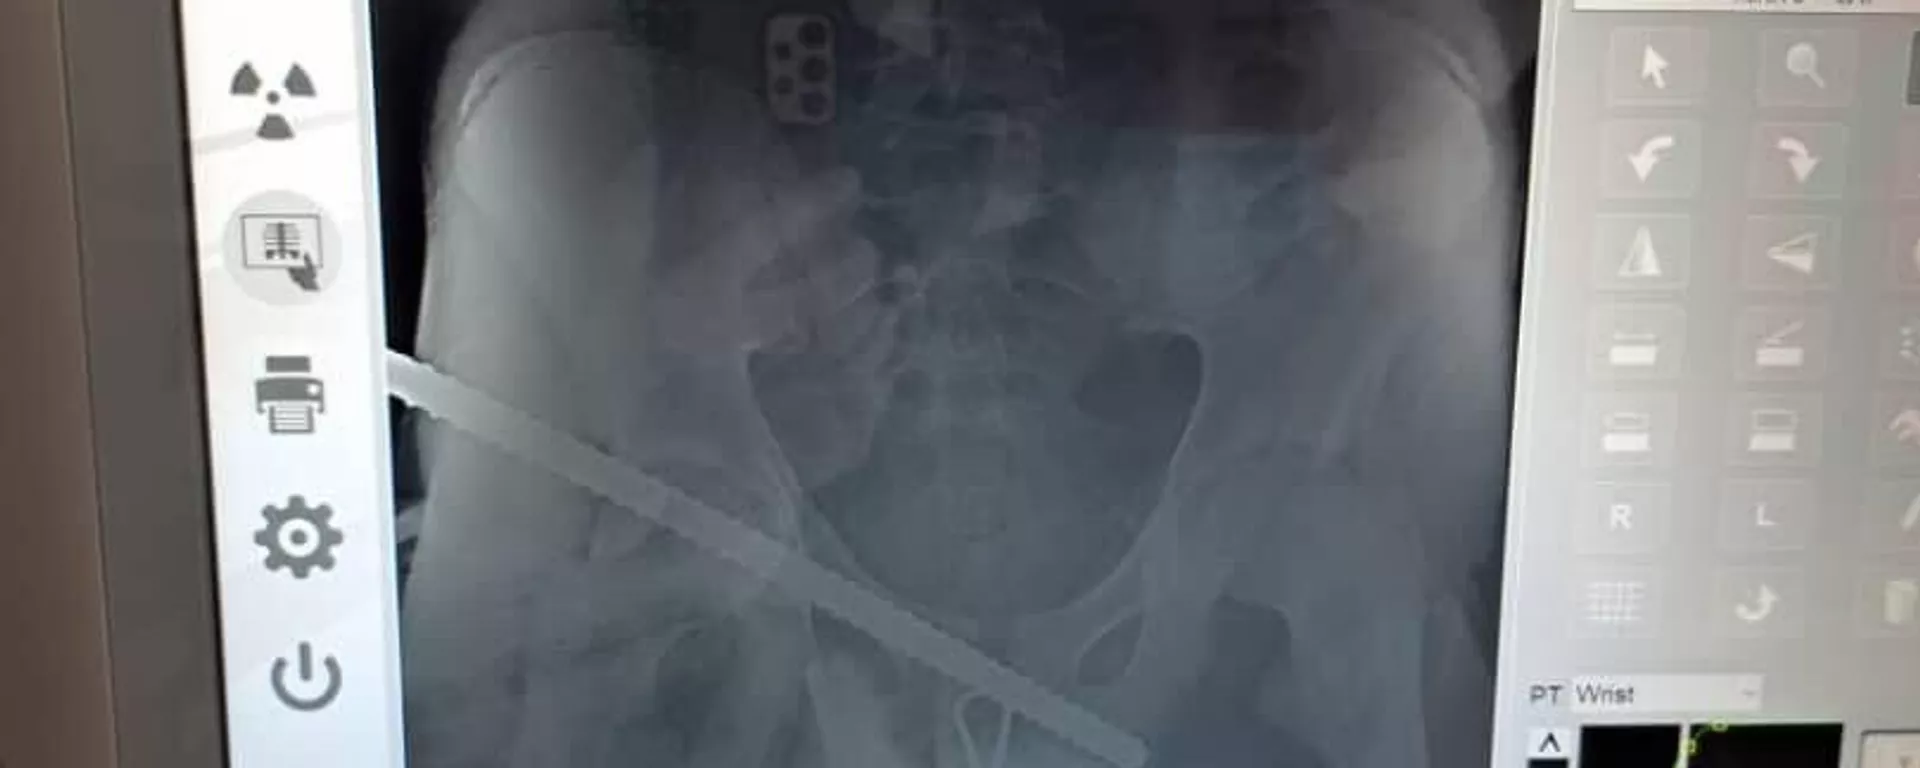

На стройке в Нарыне в подростка воткнулась арматура